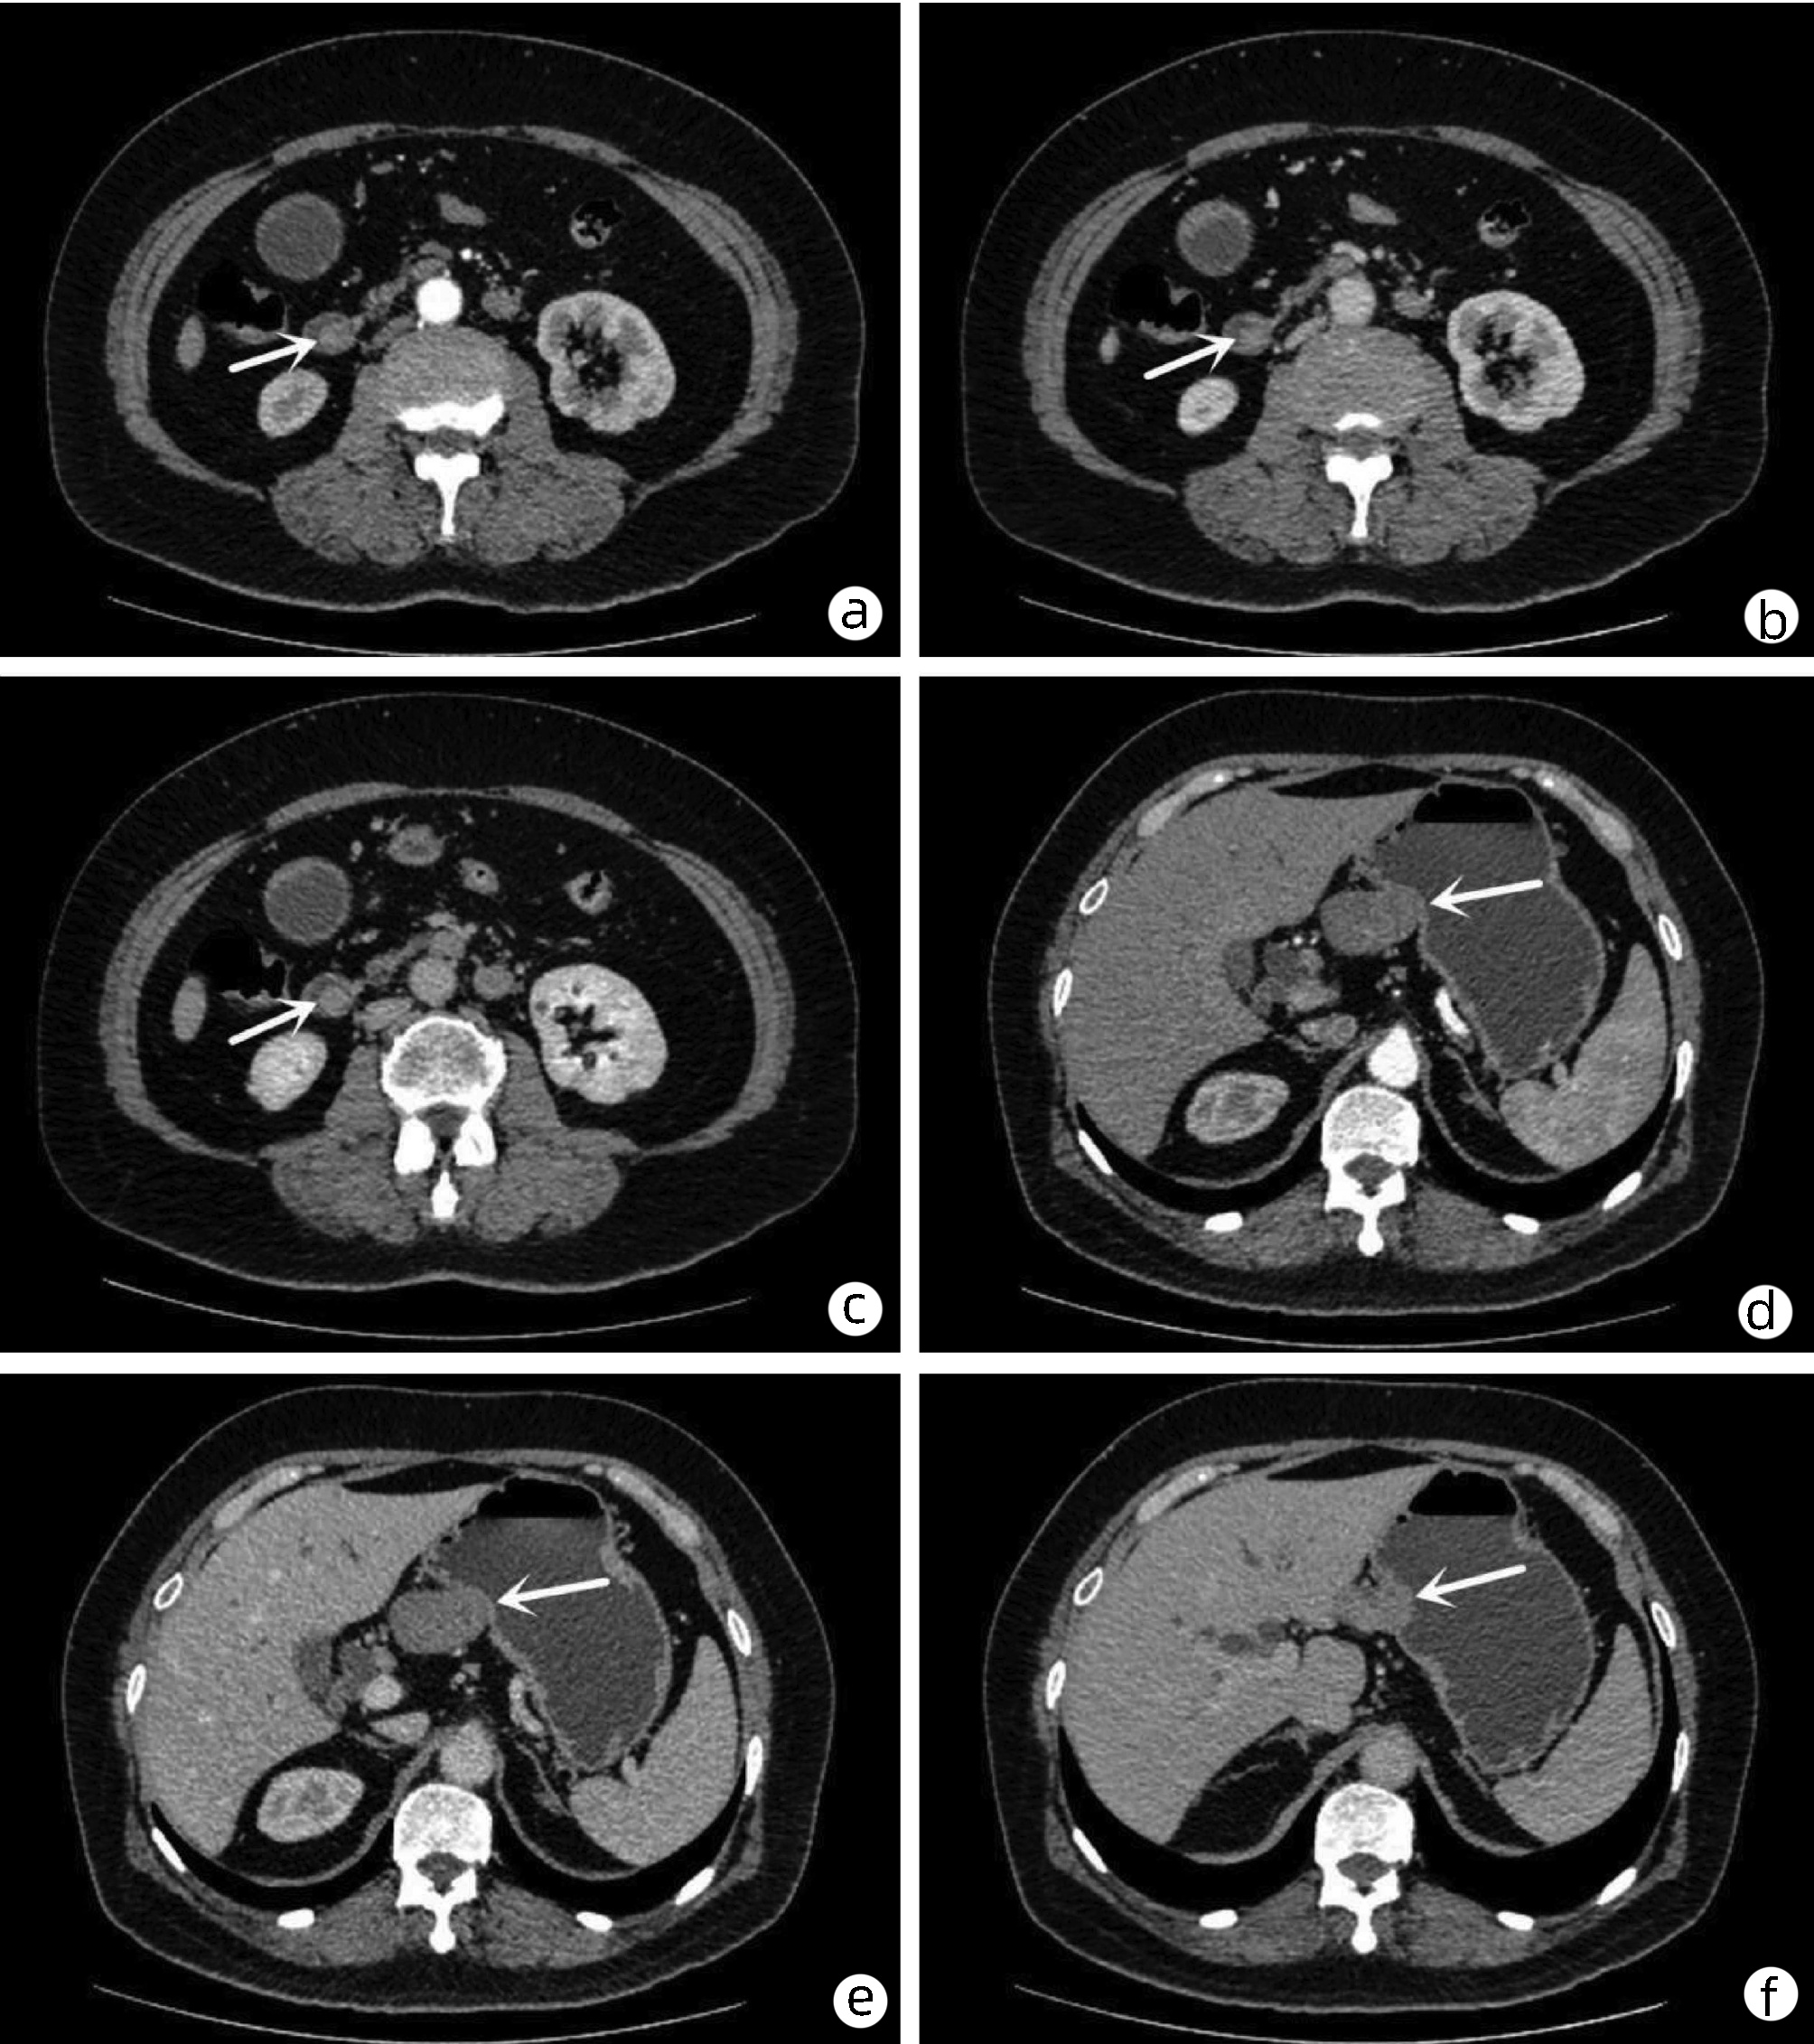

经肝动脉化疗栓塞术联合抗血管生成药基础上使用程序性死亡受体1抑制剂治疗中晚期肝细胞癌的有效性和安全性分析

丁晓鹏, 帖君, 余嘉豪, 任鹏伟, 宣国云, 马硕怡, 郭长存, 韩英, 周新民

2022, 38(5): 1086-1091. DOI: 10.3969/j.issn.1001-5256.2022.05.021

摘要(1167) HTML (400) PDF (2633KB)(90)

摘要:

目的  探讨经肝动脉化疗栓塞术(TACE)联合抗血管生成药(TKI)的基础上后续使用程序性死亡受体1(PD-1)抑制剂与TACE+TKI两种方式治疗中晚期肝细胞癌(HCC)的有效性、安全性和预后影响因素。  方法  选取2018年6月—2021年7月在空军军医大学第一附属医院所有接受TACE+TKI+PD-1抑制剂和部分接受TACE+TKI治疗的患者。收集患者的临床资料,采用倾向性评分匹配法平衡组间基线特征。计数资料2组间比较采用χ2检验,TACE次数2组间比较采用Wilcoxon秩和检验,Kaplan-Meier法分析患者的总生存期,单因素和多因素Cox回归模型分析相关预后影响因素。  结果  共筛选到181例中晚期HCC患者,其中TACE+TKI+PD-1抑制剂治疗的患者为50例,倾向性评分匹配后,纳入40例TACE+TKI+PD-1抑制剂治疗患者(观察组)和40例TACE+TKI治疗患者(对照组)。至随访截止时间,中位随访时间为28.6个月(95%CI:22.1~35.1),观察组的中位生存期为15.9个月(95%CI:7.5~24.2),对照组中位生存期为11.2个月(95%CI:5.0~17.5)。Cox回归分析提示PD-1抑制剂的应用(HR=0.42,95%CI:0.23~0.80,P=0.008)、TACE次数(HR=0.67,95%CI:0.46~0.99,P=0.043)、Child-Pugh分级(HR=2.40,95%CI:1.15~5.00,P=0.019)和血管侵犯(HR=3.42,95%CI:1.11~9.42,P=0.031)是患者预后的独立影响因素。观察组与对照组的2级以上不良反应发生率均为40%,未见显著性差异(P=0.818)。  结论  TACE+TKI+PD-1抑制剂较TACE+TKI治疗中晚期HCC患者可以明显延长患者生存期,且不良反应相对可控。